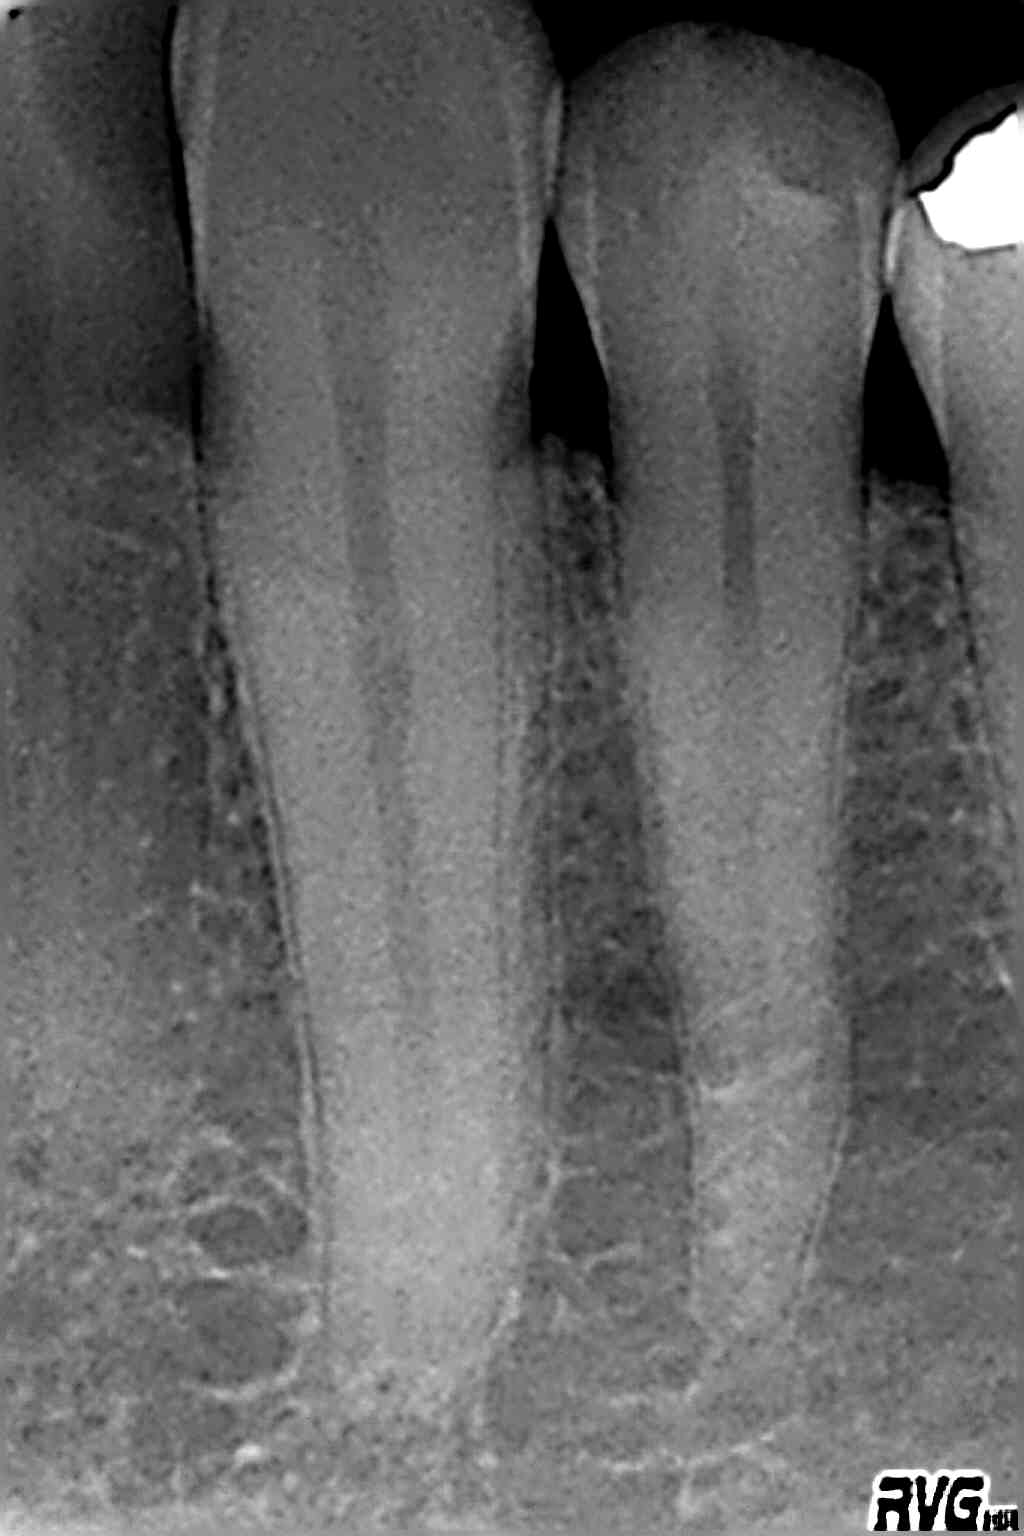

Digitales Röntgen

Röntgenaufnahmen als Einzelaufnahmen wie auch Übersichtsaufnahmen des ganzen Kiefers werden in unserer Praxis digital erstellt.

Die Strahlenbelastung gegenüber herkömmlichen Röntgenaufnahmen ist deutlich reduziert. Die Diagnostik verbessert.